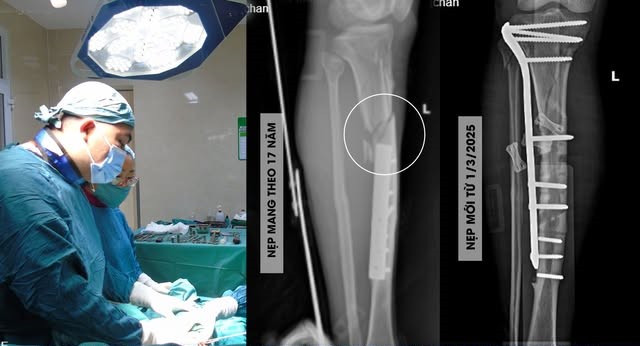

Cách đây 17 năm, sau một tai nạn, ông C, 50 tuổi, trú tại huyện Cẩm Khê (Phú Thọ) bị gãy xương chày bên trái và được phẫu thuật kết hợp xương bằng nẹp vít AO. Một năm sau phẫu thuật, mặc dù xương đã liền tốt, có chỉ định tháo bỏ nẹp vít nhưng ông C quyết định để lại và dự định mang nó theo suốt cuộc đời.

Thế nhưng, sau một tai nạn xe máy cuối tháng 2/2025, ông C bị gãy kín 1/3 trên xương chày trái, bắt buộc phải “chia tay” với khối kim loại đã gắn bó với mình suốt 17 năm để nhường chỗ cho nẹp vít mới.

| Ca phẫu thuật cho bệnh nhân - Ảnh BVCC |

BSCKII Giang Hoài Đức, Trưởng khoa Ngoại tổng hợp cho biết, bệnh nhân bị gãy 1/3 trên xương chày trái, vị trí gãy sát đầu trên của nẹp vít kết hợp xương 17 năm trước.

Quá trình phẫu thuật gặp đôi chút khó khăn khi tháo bỏ phương tiện kết hợp xương cũ do cal xương bám nẹp, lấp nẹp và đầu mũ vis, kẹt chặt thân vis trong xương, sau khi hoàn thành công đoạn này các bác sĩ tiến hành kết hợp xương chày trái bằng nẹp khóa chuyên dụng.